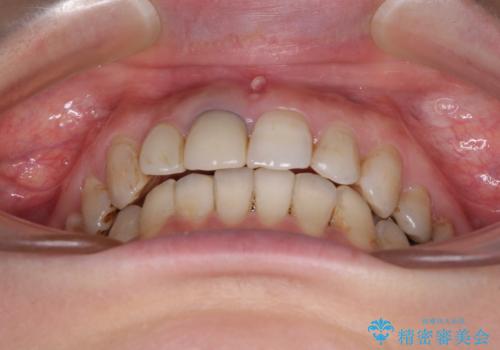

- 前歯の歯並びやむし歯治療の跡、奥歯の銀歯を気にして来院された患者様です。

インビザラインによる矯正治療の後に虫歯や銀歯をセラミックにて補綴することとしました。

前歯のむし歯治療の跡や奥歯の目立つ銀歯がなくなり、明るい口元になりました。